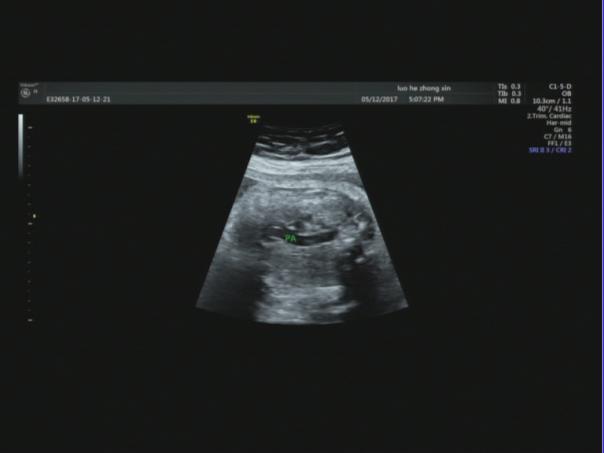

【声像图表现】 胎儿心脏:四腔心切面可显示,左心偏小,右心偏大.主动脉内径明显偏细,PA:7.1mm,PAV:84cm/s,AO:4.0mm,AOV:38cm/s,因体位限制,主动脉弓显示不清。胎儿腹部内脏:胆囊位于腹腔左侧,心脏及胃泡位于右侧胸腔,心房反位,心室左襻,肺动脉发自功能右室,主动脉发自功能左室,三尖瓣增厚,回声增强,四腔心切面可显示.左心明显偏小,右心明显扩大。因胎儿体积大位置较远,左房明显小,未探及明显的肺静脉血流信号入左房。

32周的孕妇,这次超声检查是发现胎儿肝脏,胆囊位于腹腔左侧,心脏及胃泡位于右侧胸腹腔,理论上胎儿肝脏、胆囊应位于腹腔右侧,胃泡位于腹腔左侧,心脏位于胸腔偏左侧,但是这个胎儿不仅存在着脏器反位,而且从声像图来看胃泡和心脏位于一个切面,难以分清是在胸腔还是腹腔。根据超声资料,胎儿心脏还表现左心偏小,右心偏大.主动脉内径明显偏细,因体位限制,主动脉弓显示不清。因胎儿体积大位置较远,左房明显小,未探及明显的肺静脉血流信号入左房,说明胎儿心脏也存在发育不良。

是较少见的先天畸形之一,由于膈肌的发育缺陷导致腹腔内容物疝入胸腔,发病率约为新生儿的1:2000-1:3000,约占所有产前检出胎儿畸形的3%。膈疝胎儿生后死 亡 率 可 高 达 60%,若合并其他畸形,则 死 亡 率 可 高 达 79%。国外大宗报道膈疝的产前诊断率约 59%,不同地 域之间差距较大(30%-75%)。超声可显示胎儿膈肌,正常膈肌表现为圆顶突向胸腔的薄带状低回声结构,位于胸腔与腹腔之间,紧贴肺与心脏的下面,肝脏上面,在胎儿矢状及冠状切面显示最清楚,但超声评价整个膈肌的完整性较困难,通常只有当腹腔内脏器进入胸腔内,才可能被检出膈疝典型的胎儿先天性膈疝声像图表现为正常胎儿左、右肺环绕四腔心切面特征消失,胸腔内发现占位病变。文献报道先天性膈疝以左侧多见,病变多为 混 合 性 回 声,其中胃泡回声最具有特征性,近 50%合并其他异常,其中心血管系统畸形最为常见,像这个患者就是膈疝合并左心发育不良。产妇在产前进行超声检查可有效诊断出胎儿是否具有先天性膈疝及其合并畸形,但同时,超声检查并不能检测出膈肌的缺损部位,若没有出现腹腔内脏器穿过膈肌的现象时,无法检测出膈肌的缺损程度。外院的漏诊也同样是给我们敲响了一个警钟,因此我们在进行产前超声诊断的一定按顺序,认真仔细,不遗漏我们看到的每一个部位,这既是对患者负责,也是对我们自己负责。